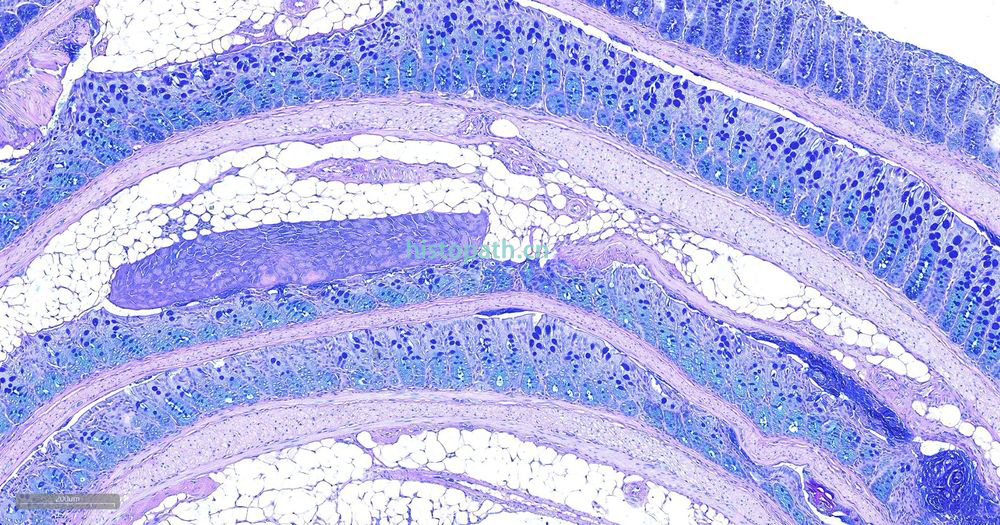

糖原染色是病理学中常规的染色方法之一,该法常用来显示糖原和其他多糖,该染色液不仅能够显示糖原,还能显示中性黏液性物质和某些酸性物质。

阿利新蓝和PAS技术联合使用可鉴别同一组织切片中的中性黏蛋白和酸性黏蛋白。这种技术也常用作广泛检测黏蛋白的手段。阿利新蓝可将唾液黏蛋白、硫黏蛋白和蛋白多糖染成蓝色。PAS技术可将中性黏蛋白染成深红/红紫色,同时将既含中性黏蛋白有含酸性黏蛋白的组织和细胞染成深浅不同的紫色,这是由于阿利新蓝与 Schiff试剂结合并反应。上述染色常可出现在含有中性黏蛋白和唾液黏蛋白的小肠杯状细胞中。

阿利新蓝是类铜钛花青染料,这种阳离子染料与酸性基团结合,也即阿利新蓝与组织内含有的阴离子基团如羧基和硫酸根形成不溶性复合物。分子中带正电荷的盐键与酸性黏蛋白多糖物质中带负电荷的酸性基团结合形成不溶性的复合物而呈蓝色,再与PAS进行复合染色,就能显示三种不同黏液物质成分。